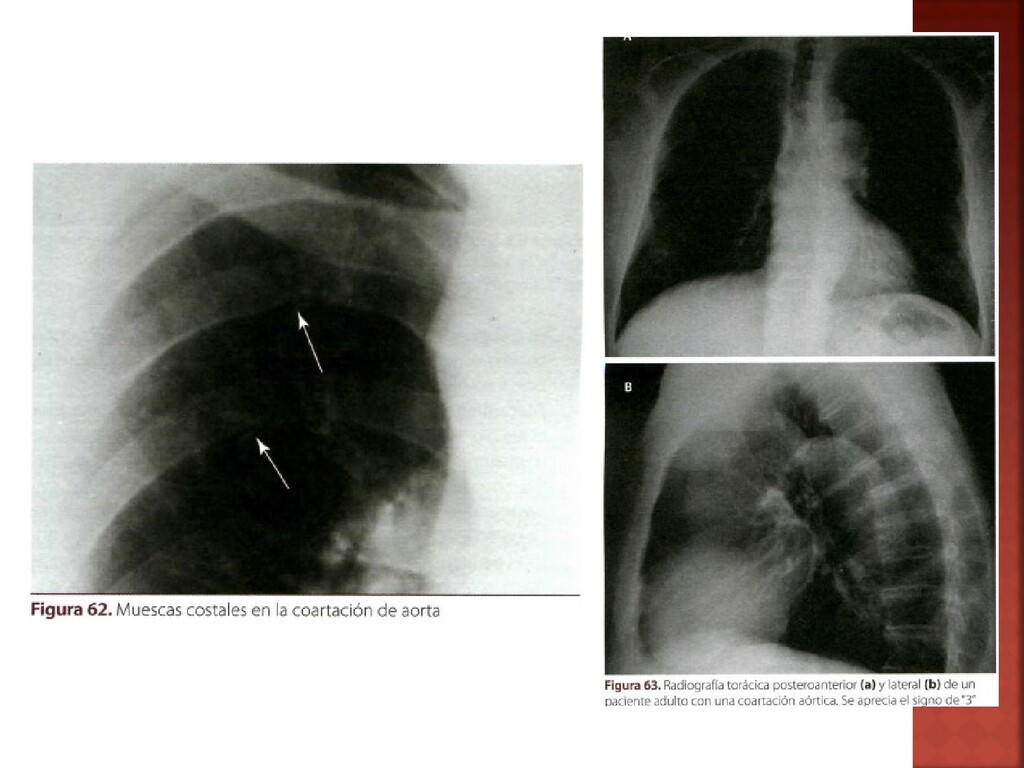

Clave • >10-20mmHg Diferencias en presión • Presencia de vasos colaterales postestenoticos • Superficie inferior de las costillas por erosión debido a la tortuosidad de las mismas Muescas de Rösler • Soplo mesosistolico en parte anterior del tórax, espalda y apófisis espinosas • Soplos sistólicos y continuos: vasos colaterales • Latido del ápex intenso Auscultación

ECG •Muescas de Rösler •Signo del “3” •Signo de la “E” (esofagograma con bario) RX TORAX •Útil para dx y seguimiento posterior •Estimar el gradiente existente en el área estenosada ECOCARDIOGRAFIA •Valores hemodinámicos de obstrucción y circulación •Necesaria? ---- INVASIVA •Indicada: coronariografia AORTOGRAFIA

29. Tratamiento de elección • QUIRURGICO Mejor edad de intervención •